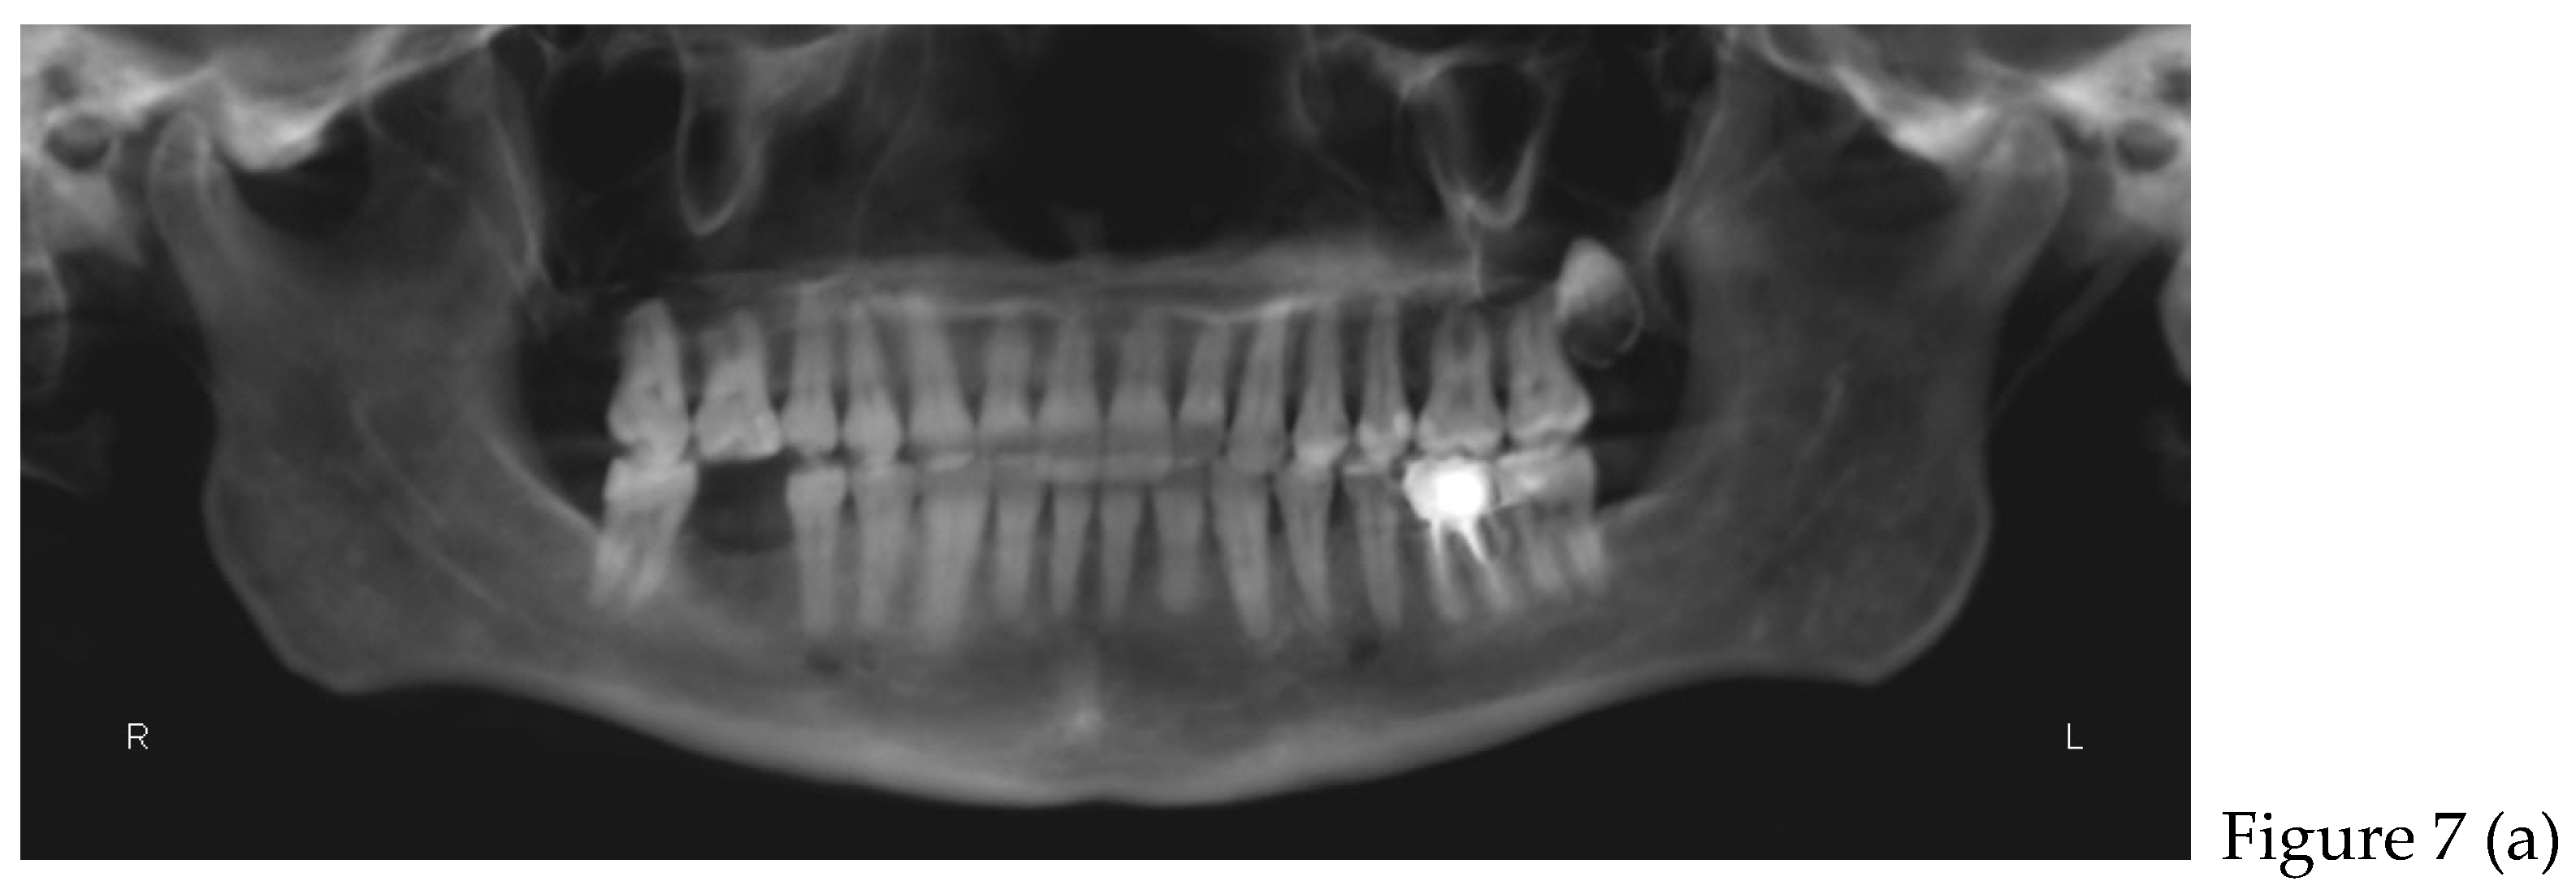

2.2. Cone Beam CT Analysis

| CBCT (t0) | |

| after 8 months | Retainers + CBCT (t1) + final photos |